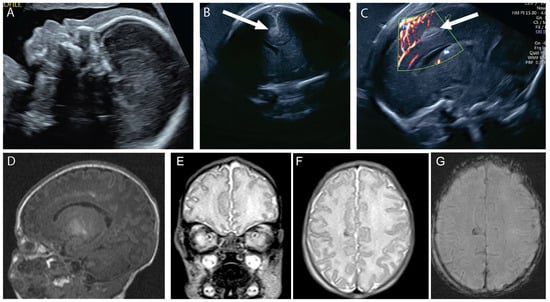

Figure 1. A 21-year-old G1P0 was referred at 16 weeks gestation for possible Blake’s pouch cyst. Her 12 week scan was notable for increased nuchal translucency. Neurosonogram at 16 weeks and 6 days tomographic ultrasound imaging (TUI) demonstrated splayed cerebellar hemispheres across multiple slice planes (lines = slice planes, upper left image) (A) and an abnormally rotated and dysplastic midline cerebellar structure, possibly representing the early fetal vermis (asterisk, (B)). These findings were readily differentiated from the referring diagnosis of Blake’s pouch cyst when additional ultrasound findings of hypersuclated parietal cortex, consistent with polymicrogyria (arrow, (C)) and hypoplastic brainstem (arrow, (B)), were also identified. Microarray was normal. MRI performed at 20 weeks and 4 days confirmed the ultrasound findings of polymicrogyria (arrow, (D)), abnormal brain stem (arrow, (E)), and hypoplastic and abnormally rotated midline cerebellar structure (asterisk, (E)). Thick and abnormal-appearing cerebellar peduncles were also noted (arrows, (F,G)). The patient elected termination. Trio exome sequencing revealed a compound heterozygous variant in PIBF1 in the fetal specimen, which is consistent with a diagnosis of Joubert syndrome 33.

In the first case, the most prominent finding was a cystic dilation of the posterior fossa at 15 weeks, which was thought to be a possible Blake’s pouch cyst, a potentially favorable prognosis. However, the hypersulcated cortex at 16 weeks was an early clue that the fetus had a more severe and global disorder of neuronal migration. The differential diagnosis of global disorders of cortical maldevelopment, impacting both the cortex and posterior fossa, include conditions along the alfa-dystroglycanopathies, other Jouberts syndrome-related disorders, or tubulinopathy spectra. These disorders have characteristic neuroanatomic findings that may allow them to be differentiated during fetal life, particularly with the help of fetal MRI, but ultimately, genetic and/or postnatal clinical diagnosis can be required for confirmation [8].